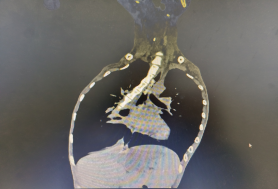

食管CT提示异物处于食管主动脉弓水平、食管第二狭窄处

患者因患有渐冻症十余年,胸廓及脊柱严重畸形、四肢肌肉萎缩、关节僵硬失去活动能力、且严重营养不良。2月22日,患者因进食时不慎将整块香肠吞下,出现胸骨后梗阻疼痛不适,大量喝水、吞咽干饭团均无法缓解症状,经UG环球国际附属第二医院食管CT检查有食管内异物,为食管内异物嵌顿,如不处理存在极大风险,最佳办法是全麻胃镜下取物。但患者身体特殊,无法满足麻醉要求,只能在普通胃镜下进行。在与患者本人及家属沟通后,接诊的张又莉医生与内二科主任徐魁、消化内镜中心主任高新生等科室医护专家团队讨论制定操作方案,于第二天进行异物取出。手术团队克服患者不能正常侧卧、没有麻醉等特殊状况下完成手术。术中患者心率一度升至170次/分,手术医生张又莉沉着冷静,5分钟顺利取出异物,术后进行完整胃镜检查提示异物取出干净,无残留,食管仅少许糜烂,患者当天顺利出院。